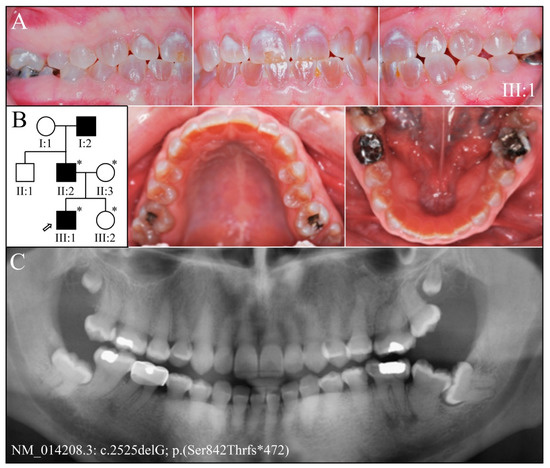

3.3. Eight Families with 3′ DSPP Mutations Causing DD-II or DGI-II

| 8 | PacBio SMRT | NG_011595.1:g.11659delG; NM_014208.3:c.2525delG; NP_055023.2:p.(Ser842Thrfs*472) | −1 Frameshift | |

| 9 | PacBio SMRT | NG_011595.1:g.11659delG; NM_014208.3:c.2525delG; NP_055023.2:p.(Ser842Thrfs*472) | −1 Frameshift | |